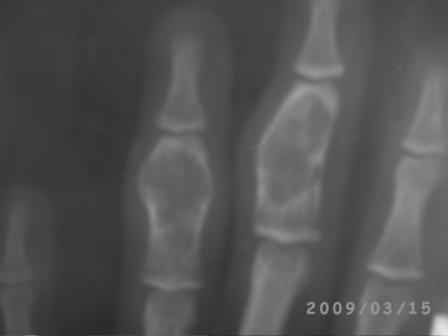

Уважаемые коллеги, на осмотре девочка 2006 г.рожд. Со слов матери 3мес. назад заметила припухлость основного фаланга 3-пальца, которая постепенно увеличилось до настоящего размера где-то в течении месяца, не болит, ребенка не беспокоит, признаки воспаления отсутствуют. Консультация онколога, биопсия - опухоль исключена (со слов матери), фтизиоортопед - тбс исключен. От основной фаланги 3 пальца к головке 4-пястной кости под кожей прощупывается хрящевидная ткань. Р-граммы от 10 декабря и 15 февраля, и фото прилагается. Что делать? Уважаемые коллеги, помогите! С уважением Абдурашид.

Добрый день, уважаемый Абдурашид. Судя по рентгенограмме, к сожалению не очень качественной, речь может идти о варианте дисхондроплазии, которую обозначают, как солитарную хондрому. Рентгенологически они проявляются в 3 вариантах-в виде интрамедуллярно и центрально расположенной энхондромы с вертеннобразным вздутием диафиза изнутри и истончением кортикальной пластинки, в виде опухоли, расположенной эксцентрично с заполнением части кортикального слоя и характерным костным козырьком, в виде экхондром, выступающих за пределы кости

Уважаемый Игорь Владимирович! Я очень рад Вас услышать! И в самом деле это один из вариантов дисхондроплазии ( т.н. болезнь Оллье), так как принесли результат биопсии: -"эмбриональный хрящевой ткань, симулирующий хрящевую опухоль"